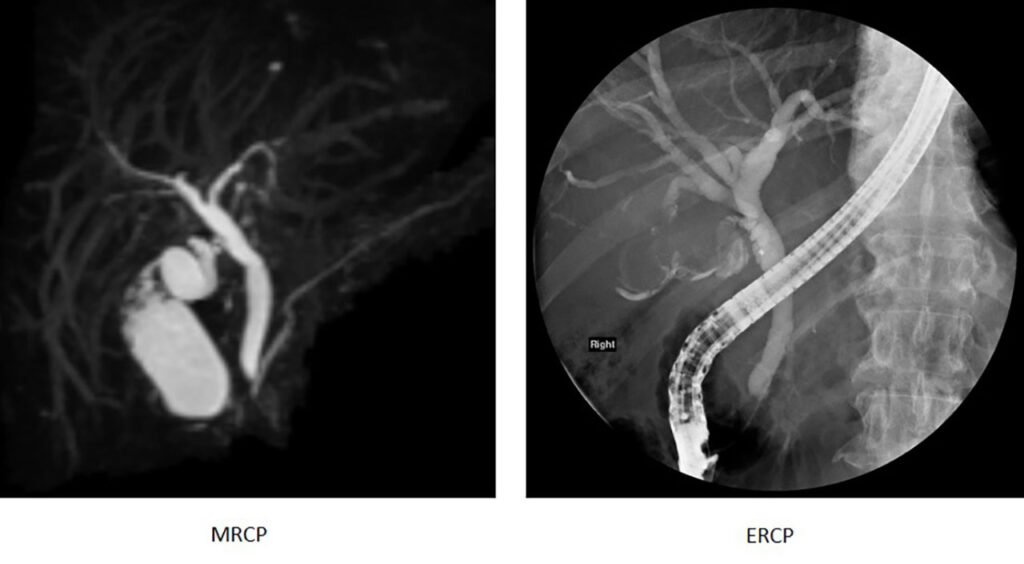

The fine-art of imaging the pancreato-biliary tree

The advent of MRCP